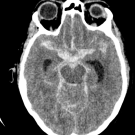

A middle-aged woman presented to the emergency department with a new-onset severe headache and progressive obtundation.